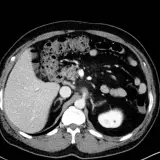

Over 2,100 interactive radiology cases, curated by radiologists for your level of training. Scroll, window, and view cases full screen — just like on PACS. Click linked findings in each writeup to jump straight to them on the image. Cases include sample reports, a focused discussion section, original illustrations, and videos.

Call Preparation — our comprehensive curriculum for junior residents preparing for call covering both classic and atypical presentations. Use the call simulator to practice a real call shift — shuffle cases, enter your own preliminary report, and receive constructive AI feedback.

PACSで期待されるツールを完備した完全インタラクティブな症例 — スクロール、ウィンドウ調整、ズーム、パン、計測、ROI、フルスクリーンモード。